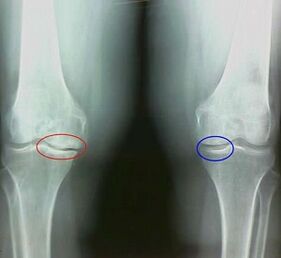

For example, what is the difference between arthritis and arthrosis of the knee joint?With arthritis, the synovial shell of joint tissues occurs.This causes an increase in temperature in the joint.

The joint joint develops, a persistent pain syndrome develops, intensifies during movement.With arthrosis, pain occurs only after physical activity, it is possible to listen to a characteristic crew or click in the articulation, gradually the articulation is deformed and loses mobility.